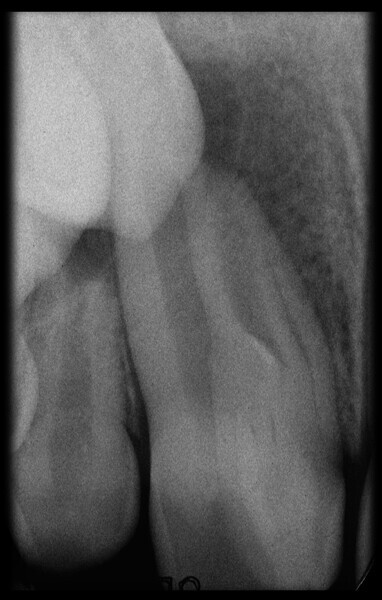

Use of 3D technology in the diagnosis and treatment of endodontic disease